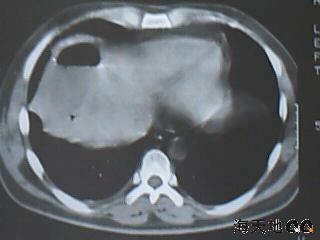

男 32y 外伤后一月余,现 t38.5,肝区隐痛。

右肝膈顶区液气平面.右膈肌增厚改变,病灶下部层面呈半月形延伸于肝表面.且于横结肠无明确密度切关系.

结合临床症状;考虑膈下脓肿.建议薄层矢状重建进一步证实.

鉴别;1,膈疝;2,间位结肠.

右隔肌与肝顶之间隙有长气液平,其下散在点状气体影,右侧腹膜局限增厚。考虑右膈下脓肿。

右膈肌增厚,肝膈间见条状低密度影内可见积气影及宽大液平面,并未见与结肠相连。因此考虑膈下脓肿。